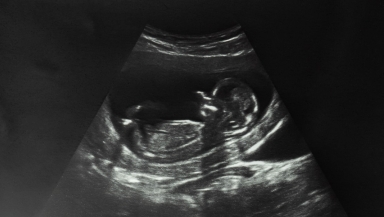

(CP) Siding with Planned Parenthood and other abortion providers in Ohio, a judge has expanded an earlier order blocking enforcement of a law that would ban most abortions after about six weeks into a pregnancy, or around the time a baby's heartbeat can be detected.

The law bans most abortions after a baby's heartbeat can be detected.